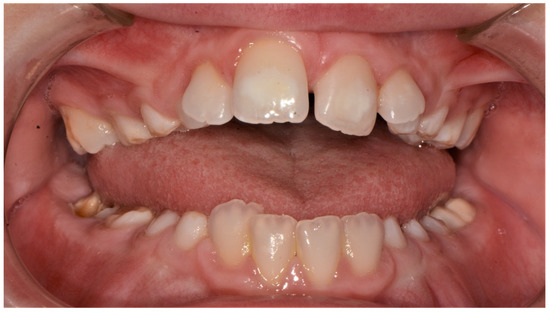

| Present study 2021 | 1 patient | M | high narrow palate, crowding, molar incisor hypomineralization (MIH), second class | 9 |